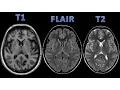

uma anjo se tem contraste ou não tem contrasto depois que você identificou a sequência aí você parte para os chados patológicos hoje nós vamos comentar Como identificar as três sequências a sequência T1 a sequência T2 e a sequência flir vamos começar pelo T2 que no crânio é um pouco mais fácil na sequência ponderada em T2 a água brilha então a água fica branca a água fica com hipersinal ou sinal hiperintenso a pergunta é onde que tem a água no crânio então o líc é predominantemente composto por água e ele está dentro dos ventrículos veja aqui

nos ventrículos laterais nos cornos frontais dos ventrículos laterais aqui os átrios dos ventrículos laterais tá brilhando tá branco tá com hipersinal Então essa sequência é uma sequência T2 porque o líquor brilha porque a água brilha no sucos corticais também temos Lor vejam os sucos corticais tê brilho eles brilham veja aqui nas cisternas licc nos ventrículos nos sucos corticais e nos olhos o humor vítreo ele tem um conteúdo de água muito grande então ele brilha na sequência ponderada em T2 Então você olhou a sequência o olho tá brilhando os sucos estão brilhando os ventrículos estão brilhando

a sequência é T2 e a sequência ponderada em T1 primeiro a gente vai procurar a água nos mesmos lugares nos ventrículos nos sucos corticais nas cisternas e no olho a água fica escura em T1 só que aqui a gente tem que tomar mais um cuidado além da água ficar Escura em T1 pra gente ter certeza que é um T1 a substância Branca fica branca e a substância cinzenta fica cinzenta então no T1 a água fica escura a substância Branca fica branca a substância cinzenta fica cinzenta se a gente parar para raciocinar um pouquinho a substância

espleno do corpo caloso e a substância cinzenta está cinza ó veja o córtex C aqui o córtex do lobo frontal córtex da ínsula e a substância cinzenta localizada profundamente no encéfalo na forma de núcleos também está cinza Veja a cabeça do núcleo caudado veja o núcleo putam o globo pálido o tálamo então substância branca branca substância cinzenta cinza líquor escuro portanto essa sequência é um T1 lado a lado para comparar diferenciar T1 de T2 vamos na água T2 a água brilha veja aqui no olho T1 a água fica escura veja aqui no olho veja nos

sucos corticais fica escuro no T1 fica branco no T2 Veja a substância Branca fica branco no T1 a substância cinzenta fica Cinzento no T1 no T2 é o contrário a substância Branca fica escura e a substância cinzenta fica mais clara por quanto mais água quanto mais conteúdo líquido quanto mais água mais branco fica no T2 o córtex tem mais água que a substância Branca então ele fica mais branco a mielina que é hidrofóbica faz com que a substância Branca tenha menas água que o córtex portanto a substância Branca fica mais escura no T2 T1 líquor

escuro substância branca branca substância cinzenta cinza T2 líquor Branco substância Branca escura substância cinzenta mais clara o contrário de T1 vamos falar um pouco sobre T1 com contraste o contraste usado na ressonância magnética é o gadolin e a gente faz o contraste sempre na sequência T1 você faz T1 antes do contraste Aí você faz todas as outras sequências T2 flare SW w de fusão e você injeta o contraste na veia e repete a sequência T1 Então você vai ter T1 sem contraste e T1 com contraste E aí você compara um com o outro o princípio

parte anterior do corpo caloso era formada não existia o restante o corpo e o esenio do corpo caloso então uma disgenesia do corpo caloso associada a um lipoma túbulo nodular agora vamos para a sequência flir sequência flir extremamente importante no crânio uma sequência obrigatória de se fazer no crânio o que que é é a sequência frear é um T2 com supressão do Lor é um T2 onde você apaga oor veja aqui é um T2 Se você apagar o brilho do Lor que está aqui nos ventrículos e nos sucos corticais vir FL veja exatamente igual T2

a substância cinzenta mais clarinha substância cinzenta mais clarinha substância Branca escura substância Branca escura só que no T2 o líquor está brilhando aqui dentro dos ventrículos e nos sucos corticais no flir você eliminou o licor Você apagou o sinal do licor então ele não tem sinal Ele fica escuro ele fica preto veja nos sucos e aqui nos ventrículos então por isso é importante que quando a gente analisar no crânio para saber se é um T1 ou é ou é um flir você tem que olhar o licor mas tem que olhar também o sinal da substância

branca e da substância cinzenta porque veja que tanto em T1 quanto no frer o líquor fica escuro mas no T1 a substância Branca fica branca a substância C cinzenta fica cinzenta no T2 é o contrário a substância Branca fica escura e a substância cinzenta fica mais branquinha o flir é um T2 onde você suprime o líquor e qual a importância da sequência flir veja aqui um T2 o exame não tá bonito o exame tá mal feito tá mexido não mal feito mas o exim tá mexido provavelmente a paciente agitada mas é um T2 vejo o